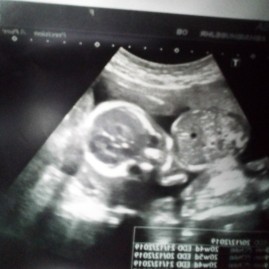

รูปใบซาว

กำหนด25ธันวาภาพซาวตอน20wได้ลูกชาย ตอนนี้23Wแล้วมีใครมองรูปน้องเหมือนแม่บ้านนี้บ้างเอ่ย เห็นตรงกับแม่รึป่าว

บ้านนี้เห็นไข่น้องชัดมากเลยค่ะ 😂😂 ซาวด์มาคือเจอเลย แถมมือน้องก็เห็นลางๆแบบนี้ด้วยนะคะ 🤣

23วีคเหมือนกันค่ะ ผ.ชค่ะ น้องนอนแอ่นตัวนอนจุ้บนิ้วพอดีค่ะ